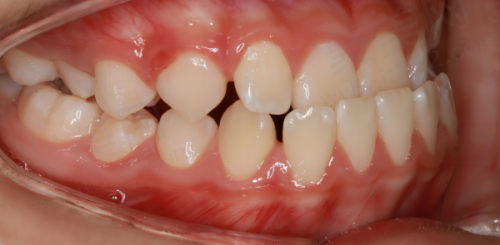

医院汇聚了国内外众多优质口腔医生资源,这些医生临床经验多,掌握着完善的口腔诊疗技术。他们在业界享有盛誉,擅长高难度的种植牙、矫正等项目。比如在种植牙方面,医生们能够根据患者的口腔情况、骨质条件等,精细地选择合适的种植体和种植方案,确保种植牙的成功几率和稳定性。在矫正项目中,医生们可以熟练运用各种矫正技术,帮助患者改善牙齿排列不齐等问题。

医院设有数字化种植中 心、数字化正畸中 心等,这些数字化技术的应用大大提高了治疗的精细度和效率。在数字化种植中,医生可以通过口腔CT等设备获取患者口腔的三维数据,然后在电脑上进行模拟种植,提前规划好种植体的位置、角度和深度,这样在实际种植过程中就能更加精细,减少手术创伤,缩短修复时间。在数字化正畸方面,医生可以利用数字化模型分析患者牙齿的排列情况,制定个性化的矫正方案,还能让患者提前看到矫正后的成效。

特别多去过医院的患者都说特别满意,认为医院正规、收费合理、医生技术好。尤其是在种植牙和牙齿矫正方面,患者对治疗成效给予了高度评价。比如有患者在种牙后,牙齿的咀嚼功能修复得良好,外观也特别自然,感觉就像自己原来的牙齿一样。还有患者在做完牙齿矫正后,牙齿变得整齐美观,自信心也提升了不少。

医院注重为每位患者量身定制治疗方案,提供个性化的服务。医生会根据患者的口腔状况、身体状况、个人需求等因素,制定更适合患者的治疗方案。比如在种植牙时,会考虑患者的骨质条件、年龄、经济情况等,选择合适的种植体和种植方式;在牙齿矫正时,会根据患者牙齿的畸形程度、咬合关系等,设计个性化的矫正方案。